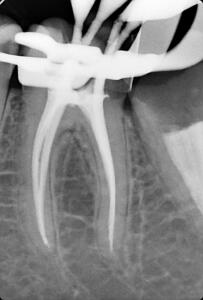

Клинические случаи в эндодонтии